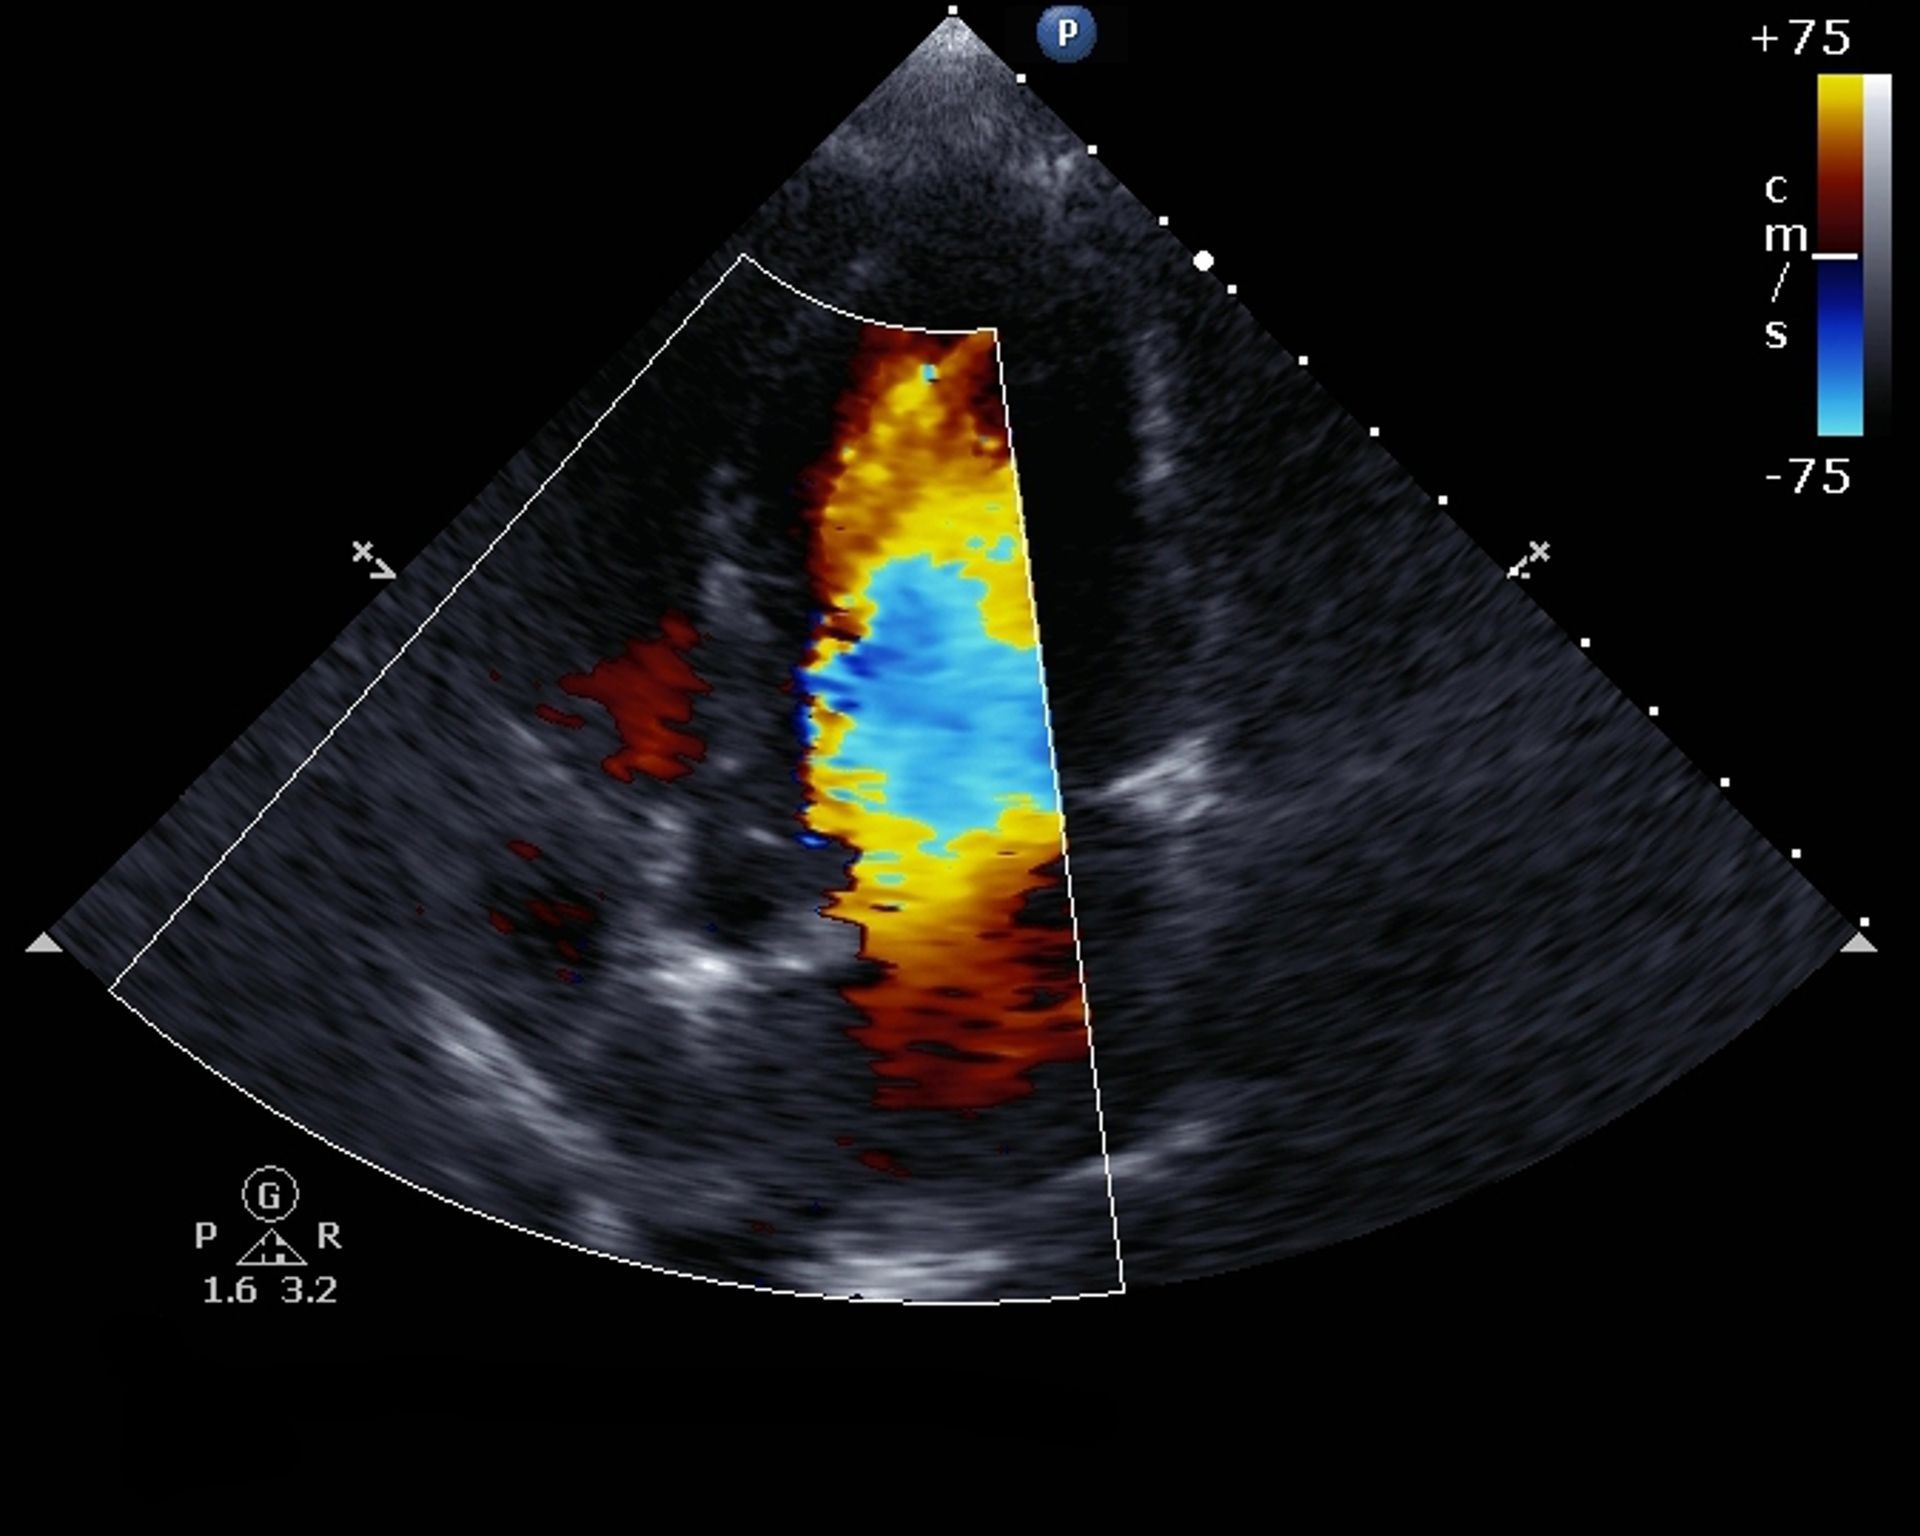

Ecografia - Ecopower-Color-Doppler

Il Poliambulatorio GRECO utilizza apparecchiature di ultima generazione per eseguire ecografie specializzate, tra cui:

- Ecodoppler dei tronchi sovraortici (TSA)

- Ecocolordoppler arterioso dell'aorta

Per andare incontro a quei pazienti che sono impossibilitati a spostarsi da casa, lo studio medico greco, previa prenotazione, esegue ecocolordoppler a domicilio. Sia in Palermo città che provincie di Palermo e trapani grazie alla disponibilità di apparecchiature portatili di ultima generazione